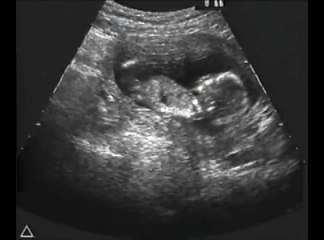

12 Weeks Pregnant Gender Determination Ultrasound

85 chance its a girl - determined at the end where the cursor is pointing\rbr\rbr*confirmed 100 at 20-week ultrasound